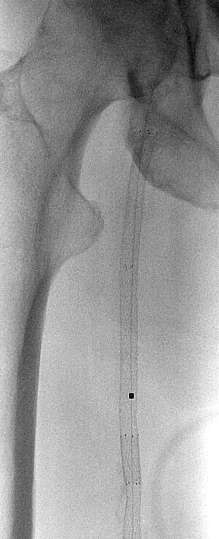

支撑架内导丝前行

从顺行途径不能够通过近端支撑架内阻塞

导丝经Outback 通过近端支撑架阻塞